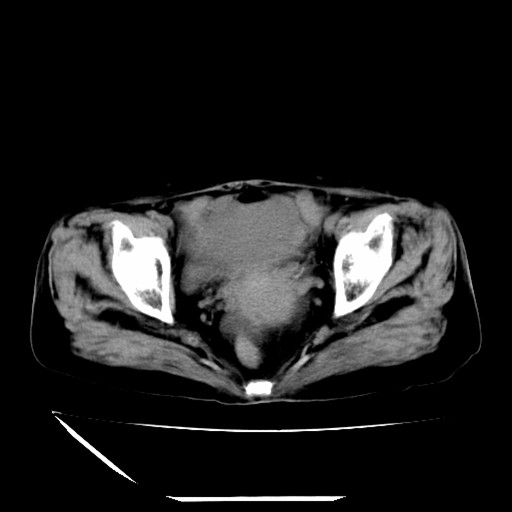

标题: CT16840:女-63岁,下腹部疼痛,

补充资料:血象是13.5,临床拟诊阑尾炎

本人诊断是右肾周围炎,阑尾炎,盆腔少许积液!

诊断右肾周围炎是因为我图像没有发完,诊断阑尾炎是因为相当于阑尾区连续两个层面可以看到增粗的阑尾显影。

支持阑尾炎!局部腹膜增厚,脂肪密度增高。应该手术治疗。